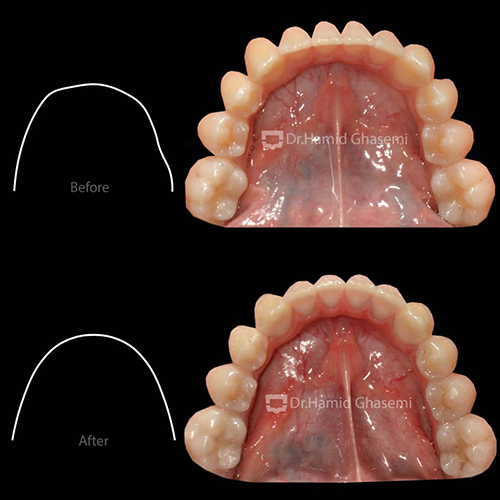

در مرحله اول، با استفاده از اکسپاندر و پیچهای داخل کامی جهت شل شدن درز بین فکی در فک بالا و سپس اعمال نیروی خارج دهانی فیس ماسک جهت جابهجایی فک بالا به سمت جلو انجام شد.

در مرحله دوم، درمان ارتودنسی ثابت با استفاده از براکتهای دیمون استفاده شد. انتخاب براکتهای دیمون جهت عریض کردن قوس فکی و دندانی انجام شد که تأثیرات آن بر عریض شدن لبخند بیمار بسیار مشهود است.

- عریض شدن فک بالا

- از بین بردن باکال کریدور (Buccal Coridor) و در نتیجه افزایش نمایش دندانها در حین لبخند